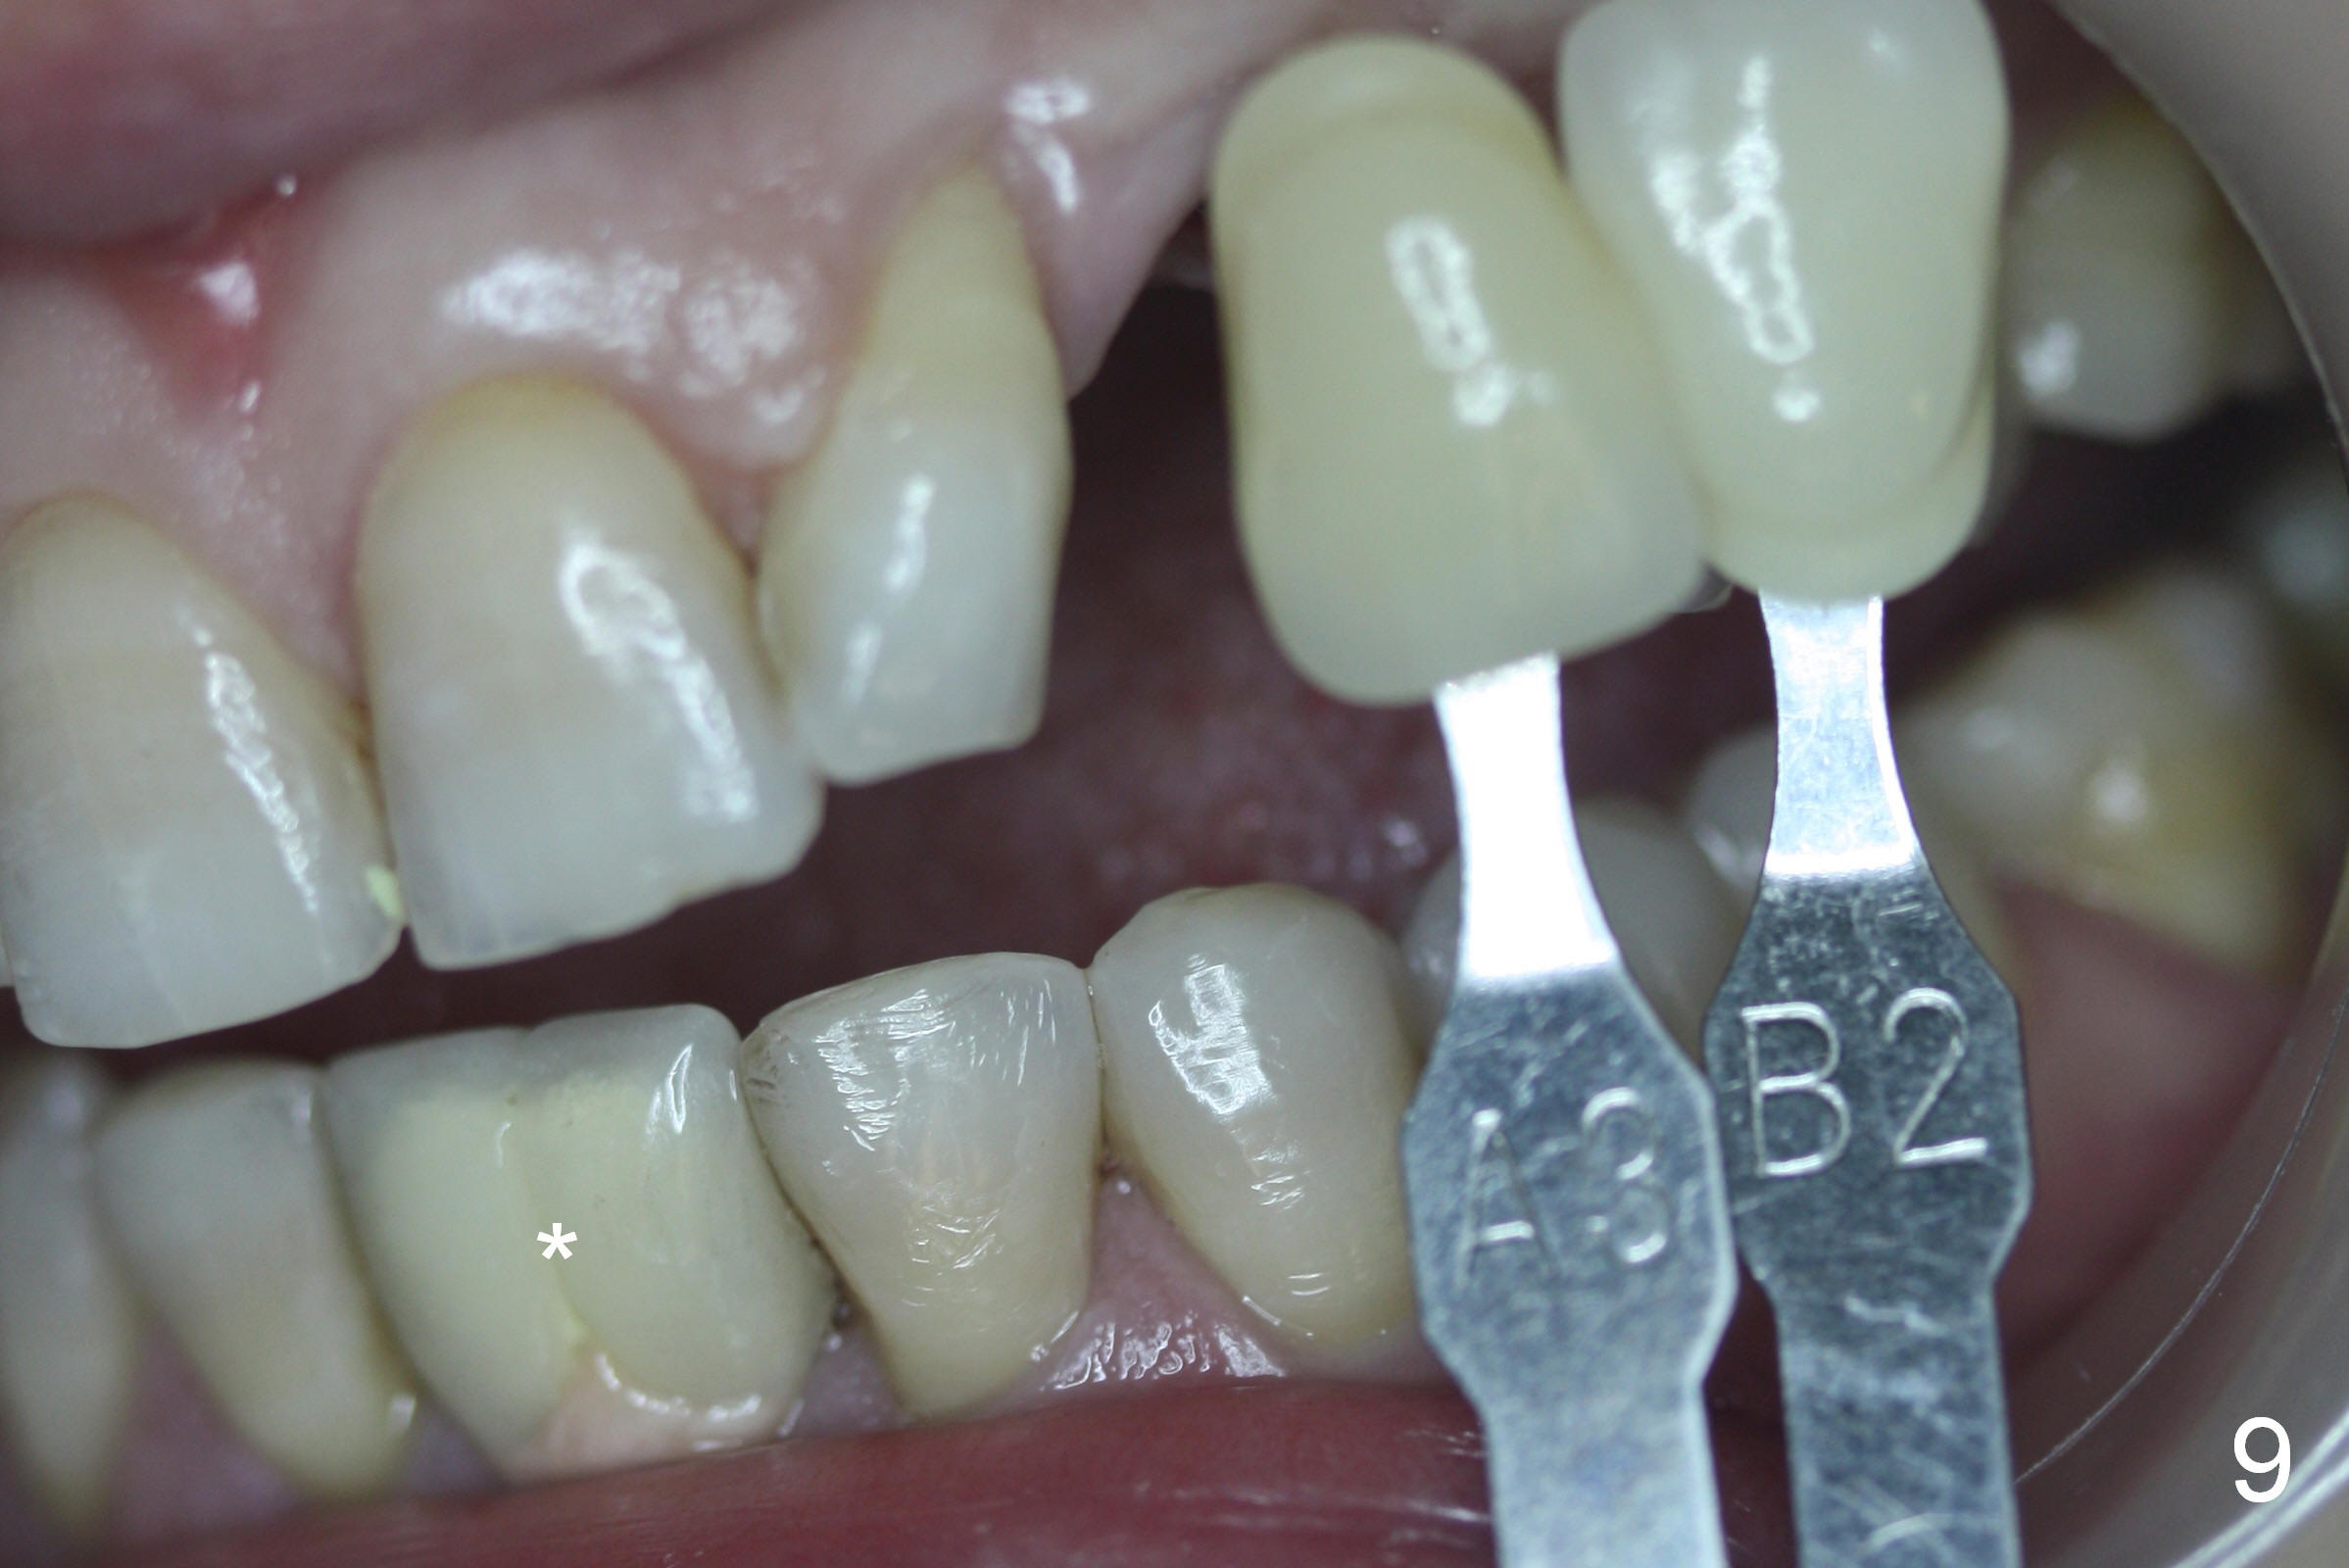

The ridge looks wide clinically 4 months post implant removal and socket preservation. In fact, the graft bone is soft and the ridge is narrow after incision. It appears that an angled 1 piece implant is an indication. A 1.2 mm pilot drill is used to start osteotomy. At approximately 17 mm, the patient feels pain. The nasal floor perforates? A 2 mm osteotome is utilized to enlarge the osteotomy. At 17 mm, the osteotome is stable (Fig.1), but the nasal floor appears out of view. Review of the preop PA shows that the distance between the gingival margin and the nasal floor (arrowheads) is ~22 mm (Fig.2). It should be safe and necessary to place a 3x20 mm 1-piece implant with 15° angulation. Insertion torque is between 40 and 45 Ncm.

Six days postop, the patient is doing fine without nasal symptoms. Nasal speculum exam does not reveal apparent nasal floor perforation. The perio dressing remains around the provisional (Fig.4,5 P). Local scaling is provided for slightly tender palatal gingiva between the provisional and the neighboring tooth (Fig.5 ^). Continuous Chlorhexidine rinse is recommended.

Eight months postop, the patient returns for #11 restoration. She reports no problem at #11, while there is light tenderness with a 2-piece implant (4.5x20 mm) at #6 at night (Fig.10, a portion of panoramic X-ray). Clinical exam reveals no abnormality at #6. Although the implant at #11 is buccally placed, there is no buccal plate atrophy (Fig.6,7). In fact the 20 mm 1-piece implant is placed in the bone (septum) between the nasal cavity (Fig.10 pink dashed line; Fig.13 (CBCT (52 year-old lady) N) and the maxillary sinus (yellow dashed line, S). In fact the apparent nasal floor indicated as arrowheads in Fig.2 and 10 is the horizontal plate of the palatine bone (hard palate)! Therefore there is no nasal floor perforation in this case. A long implant is indicated in the upper canine.

The main reason for the failure of this case is buccal placement of the implant (Fig.11 A: abutment). Every time an implant is placed at the upper anterior, make sure that palatal placement is done (Fig.12 *). The most critical step is the 1st pilot drill. If the position is not ideal, use a Lindemann bur for adjustment. Check repeatedly. If the implant starts to be deviated buccally, remove the implant, use the Lindemann bur to remove more of the palatal bone and place the implant palatally.